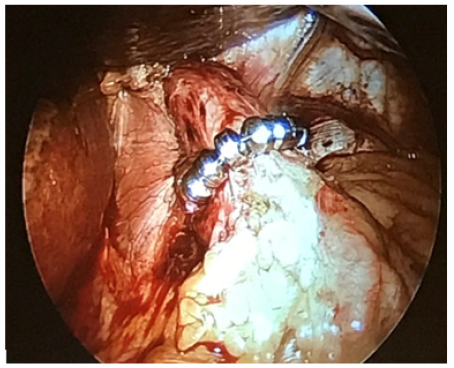

LINX Reflux Management Surgery is a band which is made up of magnetic beads covered by titanium casing and interconnected by titanium wiring. The core is made up of magnet [3]. The magnetic core allows the structure to stay in contracted form at rest as shown in Figure 1 [6]. When the bolus passes the ring expands and lets the food pass to the stomach as shown in Figure 2A [7]. The force with which the bolus passes from oesophagus to stomach is higher compared to the force with which bolus passes from stomach to oesophagus as shown in Figure 2B [7]. The device is available in multiple sizes ranging from 13 to 17 beads. Patient is under general anaesthesia; four incisions are made same as in Nissen Fundoplication. A tube is inserted with light and camera which helps the surgeon throughout the surgery [4,5]. The pars flaccida of the gastrohepatic ligament is opened to expose the right crus of the diaphragm. The appropriate position of the MSA device is two centimeters proximal to the gastroesophageal (GE) junction as determined laparoscopically by the gastric fat pad. The ends of the device and locked and placed in position as shown in Figure 3 [8].